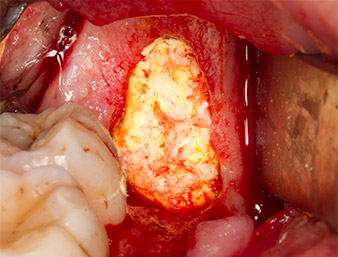

To obtain autogenous material for subsequent wound treatment, healthy bone chips were harvested from the surroundings of the root remnant with a piezo surgical instrument (Piezomed B5) (Fig. 5).

The autogenous tissue was removed with the scraper-shaped section of the working part of the instrument and stored in a physiological saline solution until further use (cf. Fig. 13).

Subsequently, the autogenous bone tissue (Fig. 13) was placed into the alveole and the surrounding bone defect (Fig. 14). Collagen fleece covered the bone chips up to bone level as protection for the exposed nerve (Fig. 15). Sutures using vicryl thread, USP 4.0, were used to close the opened up soft tissue (Fig. 16). An Ibuprofen preparation (Seractil 400 mg, 3x1) and an antibiotic consisting of amoxicillin and clavulanic acid (Augmentin 1 g, 2x1) were prescribed postoperatively.